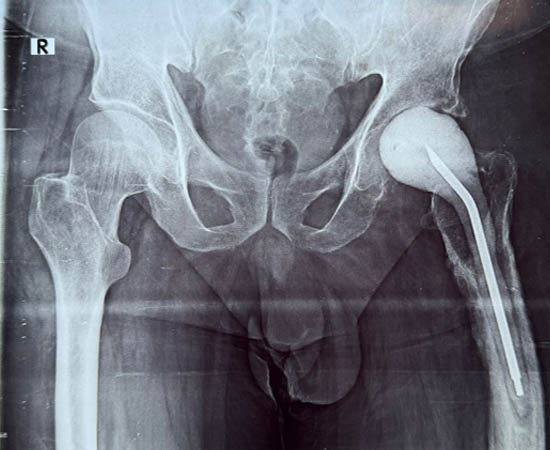

Pre Operation

Post Operation